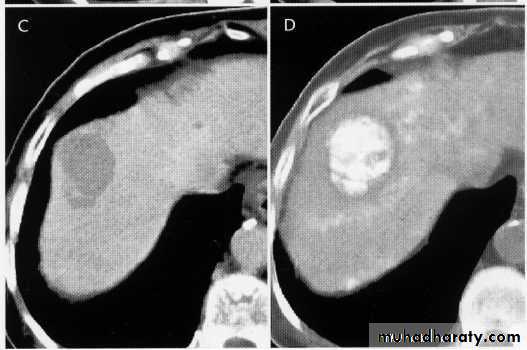

hemangeoma